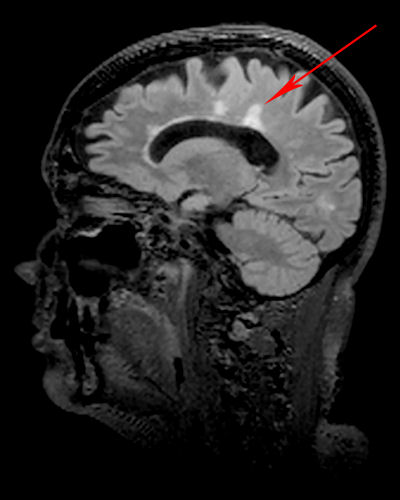

MS characteristic lesions